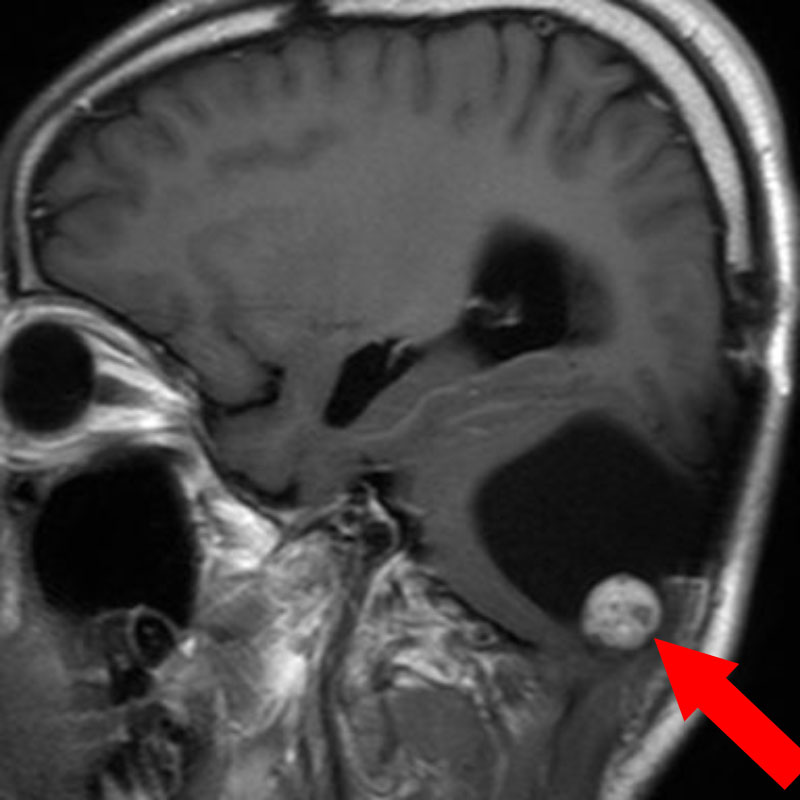

517

'24年3月

10代

小脳血管芽腫

頭蓋内腫瘍摘出術

No.’24_19 手術前1

No.’24_19 手術前2

No.’24_19 摘出 前

No.’24_19  摘出 中

No.’24_19 摘出 後